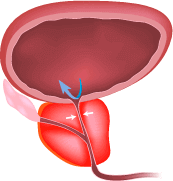

Eliminar eficazmente los síntomas y las causas de la prostatitis

(ayuda a aliviar la inflamación, eliminar el estancamiento en la pelvis, disminuye el tamaño de la próstata)